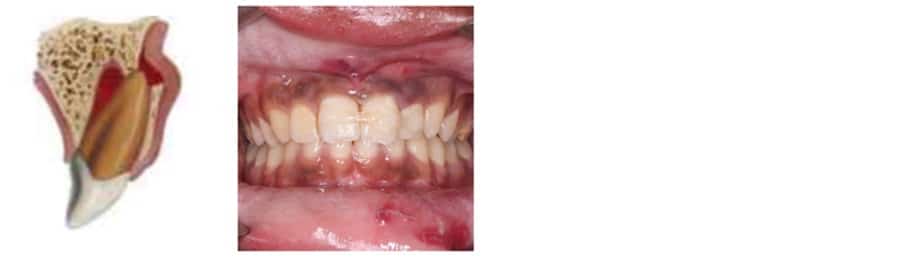

Case 1

- 18 month old child

- MH: Fit and well

- Attended with mother

- Fell off chair and hit a table

Describe what can you see?